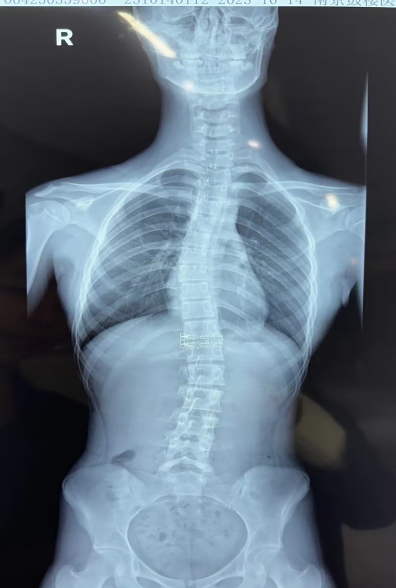

1.脊柱侧弯:尤其是青少年时期未被发现的轻度脊柱侧弯,最终会导致肩膀不对称,如青少年特发性脊柱侧弯(AIS)。

当然,也可以寻求专业帮助:康复医师可辅助进行手法松解、肌肉激活训练。如怀疑有脊柱侧弯,建议拍摄脊柱全长x线并咨询骨科医生。